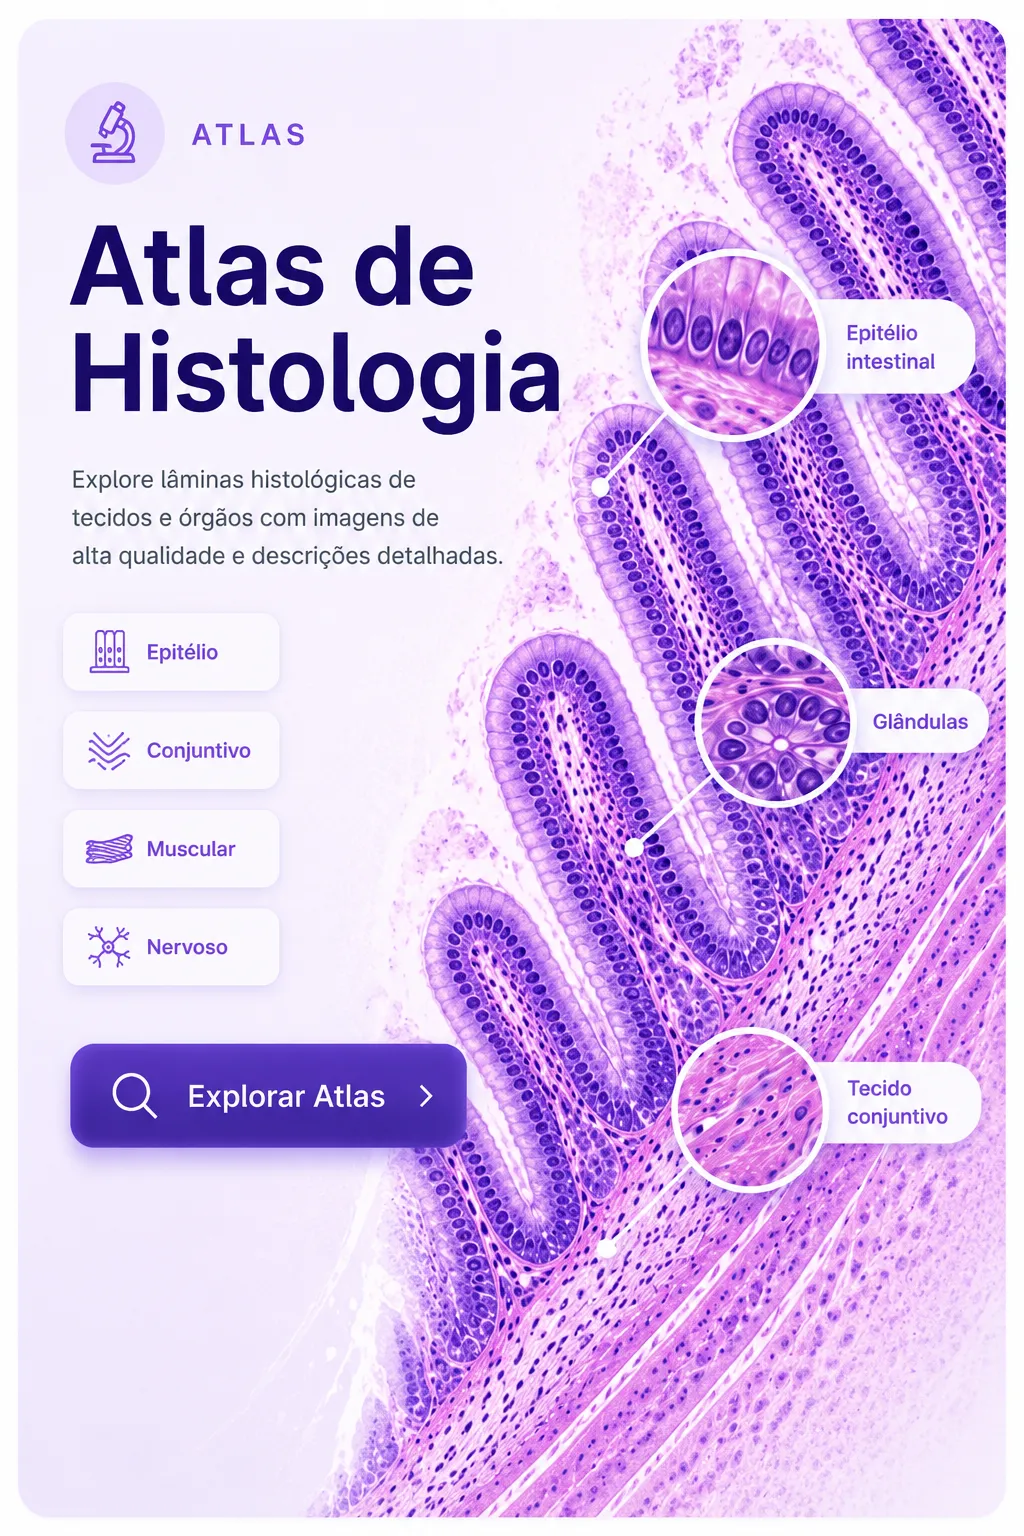

Abrir ferramentaTecnologia visual aplicada ao estudo e à consulta médica.

Explore atlas médicos em alta definição, conteúdos visuais e um guia amplo de zoonoses em uma experiência rápida, organizada e desenvolvida para a prática clínica.

Ler maisAprenda medicina de forma visual.

Explore imagens clínicas e lâminas em alta definição, organizadas para facilitar a identificação de estruturas, doenças e achados importantes no estudo e na prática médica.